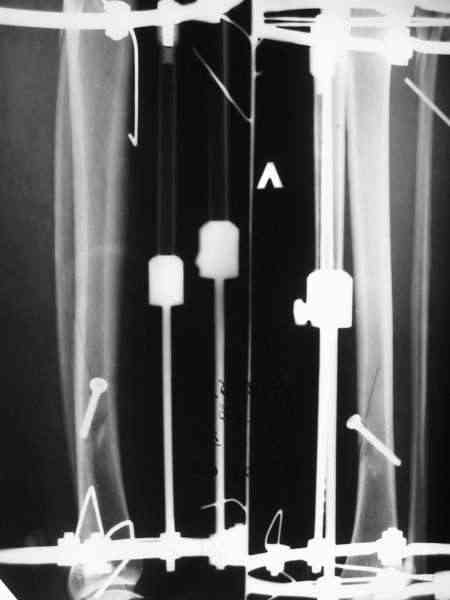

На неделе встретилась пациентка, которой выполнил около 1,5 лет назад остеосинтез голени по поводу закрытого винтообразного перелома н/3 б/берцовой кости и в/3 м/берцовой кости со смещением.

По ряду причин пришлось применить следующий метод (см. вложение).

В приватной беседе с коллегой было высказано мнение, что данный подход к лечению таких переломов дискредитирует как методику остеосинтеза по Илизарову, так и погружной остеосинтез по АО. Дискуссия дошла до того, что я к концу уже почти уверовал, что перелом сросся не благодаря, а вопреки лечению. Такой же остеосинтез с открытой репозицией, фиксацией позиционным винтом и шинированием в аппарате Илизарова было выполнено еще одной пациентке. Исход - аналогичный.